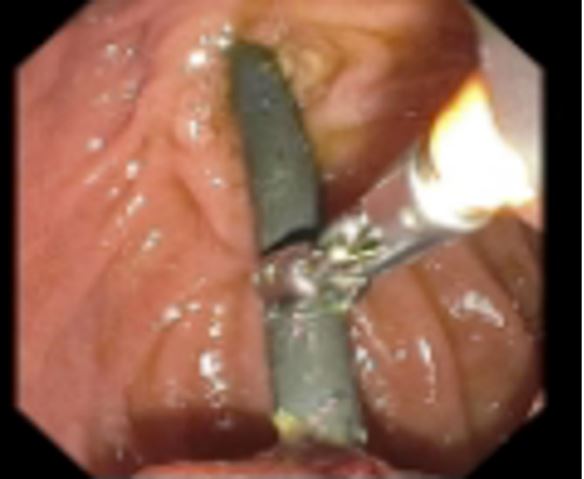

The patient was brought in for an emergent repeat ERCP. During the procedure, it was noted that the distal tip of the biliary stent had invaginated into the lateral wall of the duodenum or possibly extraluminal in the retroperitoneal space (Figures 1-3). Patient was then admitted, and general surgery was consulted. He was taken to surgery where it was confirmed that the single pigtail biliary stent had eroded through the duodenum. Procedures performed during surgery included a bile duct exploration, cholecystectomy, choleoducoduodemostomy, and duodenal repair. Patient was treated with intravenous Zosyn while hospitalized. Post operatively the patient responded well with routine post operative care, antibiotics, and fluids.

Figure 2: ERCP showing biliary stent invaginating through duodenal wall, opposite Ampulla.

Figure 3: Computed tomography impression: Stent seen in the dilated common hepatic and common bile ducts to the duodenum. The common bile duct (CBD) is normal size. Common hepatic duct and intrahepatic biliary duct are dilated. Pancreatic duct is not dilated.